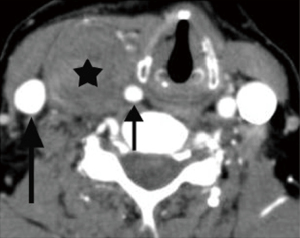

Schwannomas are benign tumors arising from Schwann cells surrounding peripheral nerves. Schwannomas in the carotid space most commonly stem from the vagus nerve. The tumor is usually a sharply demarcated round or oval mass with hypo-, iso-, or hyper-attenuation. Cystic degeneration, xanthomatous change, or areas of relative hypocellularity adjacent to densely cellular or collagenous regions usually contribute to heterogeneity of the tumor (Figure 1) (9,10). Schwannomas are hypovascular tumors, but in dynamic scans, they can show marked enhancement due to pooling of contrast agent resulting from poor venous drainage (11). More often, schwannomas demonstrate a variable degree of enhancement, most commonly patchy enhancement (Figures 2-7).

Due to its location between the vein and artery in the carotid space, schwannomas of the vagus nerve tend to separate the artery and vein, usually displacing the CCA/ICA medially and the IJV laterally (Figures 2,3) (12). Some schwannomas of the vagus nerve may displace the IJV and ICA/CCA in a posterior direction without splaying them and there is usually separation between the artery and vein (Figure 4). The cervical sympathetic chain runs in a fascial reflection posterior and slightly medial to the carotid space. Hence, schwannomas of the sympathetic chain tend to displace the IJV and CCA/ICA together, usually anteriorly and laterally (Figure 5) (5). A large schwannoma of the sympathetic chain may distort the surrounding anatomy and result in a posterior displacement of the carotid vessels without separation of the artery and vein (Figure 6) (13,14). Occasionally, a schwannoma of the cervical sympathetic chain may splay the internal and external carotid arteries at the carotid bifurcation but without encasing the arteries (Figure 7) (5). In these regards, the position of the tumor relating to the vessels in the carotid space is more important than the direction of vascular displacement. There has also been a reported case of schwannoma arising from the glossopharyngeal nerve in the carotid space causing posterior displacement of the ICA (15).